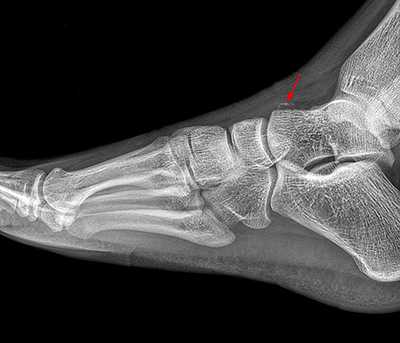

Рентгенологическое исследование

Для диагностики повреждения сустава Шопара делают рентген, КТ и МРТ. На передне-задней рентгенограмме определяют величину пяточно-кубовидного угла. Проводят одну касательную к наружному краю кубовидной кости и вторую касательную к наружному краю пяточной кости. В норме угол между касательными колеблется в пределах от 0 до 5°. Увеличение угла свидетельствует о нарушении стабильности пяточно-кубовидного сочленения. КТ во фронтальной и сагиттальной плоскостях позволяет выявить дефект суставных фасеток, смещение костей при вывихе и фрагментацию костей при переломе. КТ, по сравнению с рентгенографией, является более информативным методом диагностики. МРТ позволяет выявить дефекты отдельных связок.

Рис. 6. Отрывной перелом по тылу таранной кости на границе с суставом Шопара

При рентгенографии все снимки выполняются в сравнении со здоровой стопой. Существует несколько основных рентгенологических признаков повреждения сустава Лисфранка. 1. Отсутствие параллельности медиального края основания 2-й плюсневой и медиального края медиальной клиновидной кости 2. Расширение между основаниями 1 и 2 плюсневых костей 3. Наличие костного фрагмента в области основания 2-1 плюсневой кости 4. Тыльный подвывих на боковой проекции 5. Разрыв линии предплюсне-плюсневого сочленения.